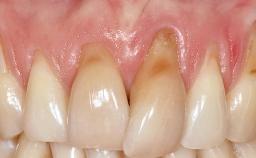

Early Implant Placement, Contour Augmentation, and Autologous Connective-Tissue Graft Using a Tunneling Technique to Replace an Upper Incisor with Generalized Gingival Recession

Variations in soft-tissue volume, evidenced either by an overabundance (Evian and coworkers 1993; Levine and McGuire1997; Dolt and Robbins 1997) or by a deficiency of soft or hard tissue can complicate implant-supported rehabilitations in the esthetic zone (Lorenzana 2008; Lorenzana and coworkers 2009). The present case illustrates the replacement of a failing upper left lateral incisor complicated by generalized severe gingival recession in the esthetic zone.